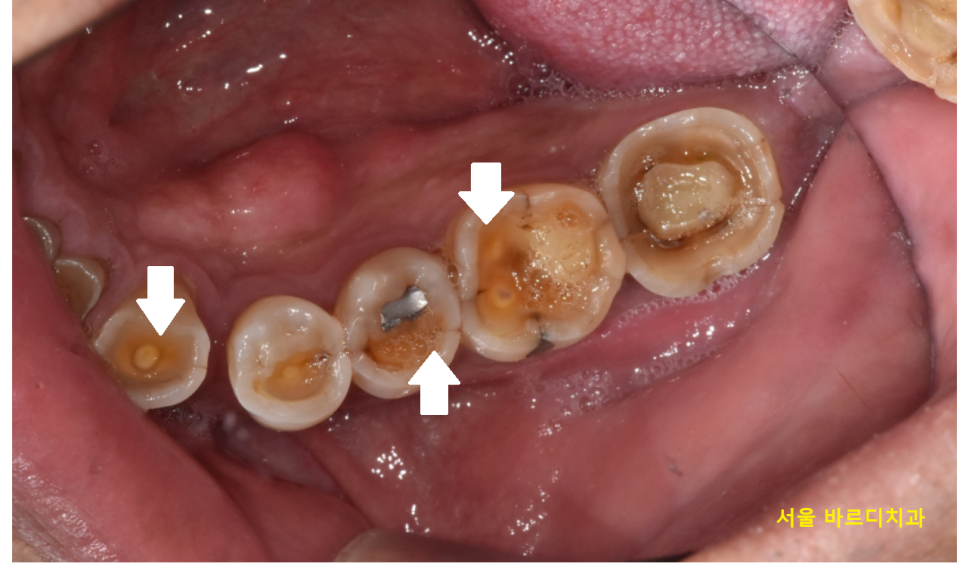

▼실제 구강▼

23.10.10

환자분들이 생각하시는 치아는

하얀 이미지이실겁니다.

환자분은 노란 부분이 많이 보이죠?

치아는 3가지 구조로 이루어져있습니다.

치아가 많이 닳다보면

치아 내부 상아질층 색깔인

노란 부분이 드러나게 됩니다.

환자분 치아처럼요!